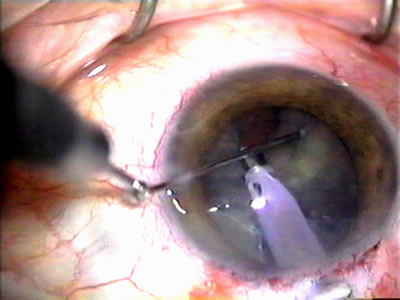

Fig. 4. Viscocanalostomy with deep sclerectomy and phacoemulsification. Nonpenetrating filtration procedures (NPFS) may be combined with phacoemulsification. Patients with mild disc damage and a history of limited topical drug therapy are the best candidates. Patients who require an IOP in the low teens are not good candidates for NPFS. By definition, NPFS is designed to lower IOP without penetrating into the anterior chamber, thereby avoiding the complications associated with trabeculectomy. Viscocanalostomy is intended to allow aqueous to percolate through a trabeculodescemetic membrane into a subscleral cavern created by the deep sclerectomy. The aqueous diffuses from the cavern into the dilated ostia of Schlemm's canal and into the episcleral venous plexus. A. Fashion a uniform 300-micron superficial scleral flap 1 mm into clear cornea. B. Construct a second 600-micron deep flap that facilitates the unroofing of Schlemm's canal, seen as the darker area. C. Use viscoelastic to dilate the ostia of Schlemm's canal. The major problem with viscocanalostomy is the eventual closure of the ostium decreasing flow to the episcleral plexus. D. Dissect the deep flap anteriorly into clear cornea creating the trabeculodescemetic membrane. This membrane is clearly seen between the scleral spur and the bend of the deep flap. The integrity of this membrane ensures the nonpenetrating portion of the surgery. Another problem with NPFS is the eventual fibrosis of this initially transparent membrane requiring goniopuncture. E. Deep sclerectomy gets its name from removal of the deep flap. Removal of this flap creates the potential subscleral space for accumulation of aqueous before it enters Schlemm's canal and exits the episcleral venous plexus. After removal of the deep flap, the superficial flap is sutured into place and conjunctiva closed. Approximately half of these procedures develop a shallow bleb.